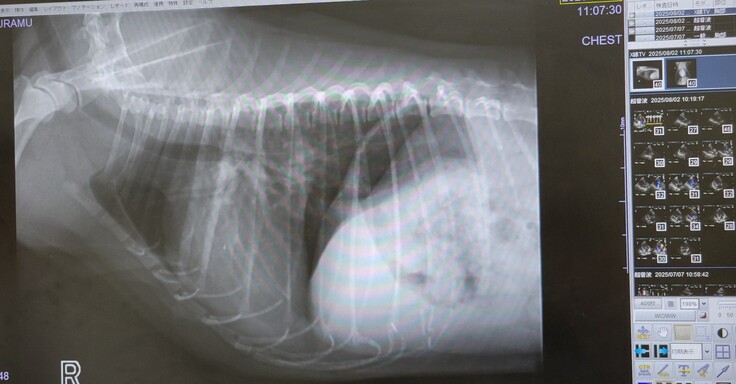

退院後1カ月の検診

本日は、ぷらむが退院してから約1か月後の検診に行ってきました。

結論としては、経過良好だったので、一安心です。

そして、かねてから心配であった咳の症状については、なんとレントゲン・エコー検査共に悪い部分が見当たらず問題なさそうで、手術時に横隔神経が一部麻痺となった部分の気管支に原因があると想定し、新たに気管支拡張の薬をいただき、経過観察することとなりました。

疑わしき影・モヤはありませんでした。

なにはともあれ肺水腫の再発ではなかったことに一安心です。